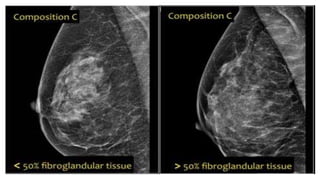

COMPOSITION-C

● The breasts are

heterogeneously

dense.

COMPOSITION-C ● The breastsare heterogeneously dense. ● Some areas in the breasts are sufficiently dense to obscure small masses.

• #10 left example the composition is c - heterogeneously dense, although the volume of fibroglandular tissue is less than 50%. The fibroglandular tissue in the upper part is sufficiently dense to obscure small masses. So it is called c, because small masses can be obscured. Historically this would have been called an ACR 2: 25-50% density. The example on the right has more than 50% glandular tissue and is also called composition c.